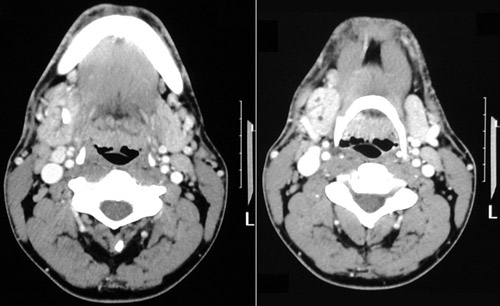

![]() | This head CT reveals a calculus within the submandibular gland in the panel on the left above. Obstruction has resulted in inflammation (producing more brightness) and duct dilation within this gland, seen in the panel on the right, which is much larger than the opposite normal submandibular gland. |